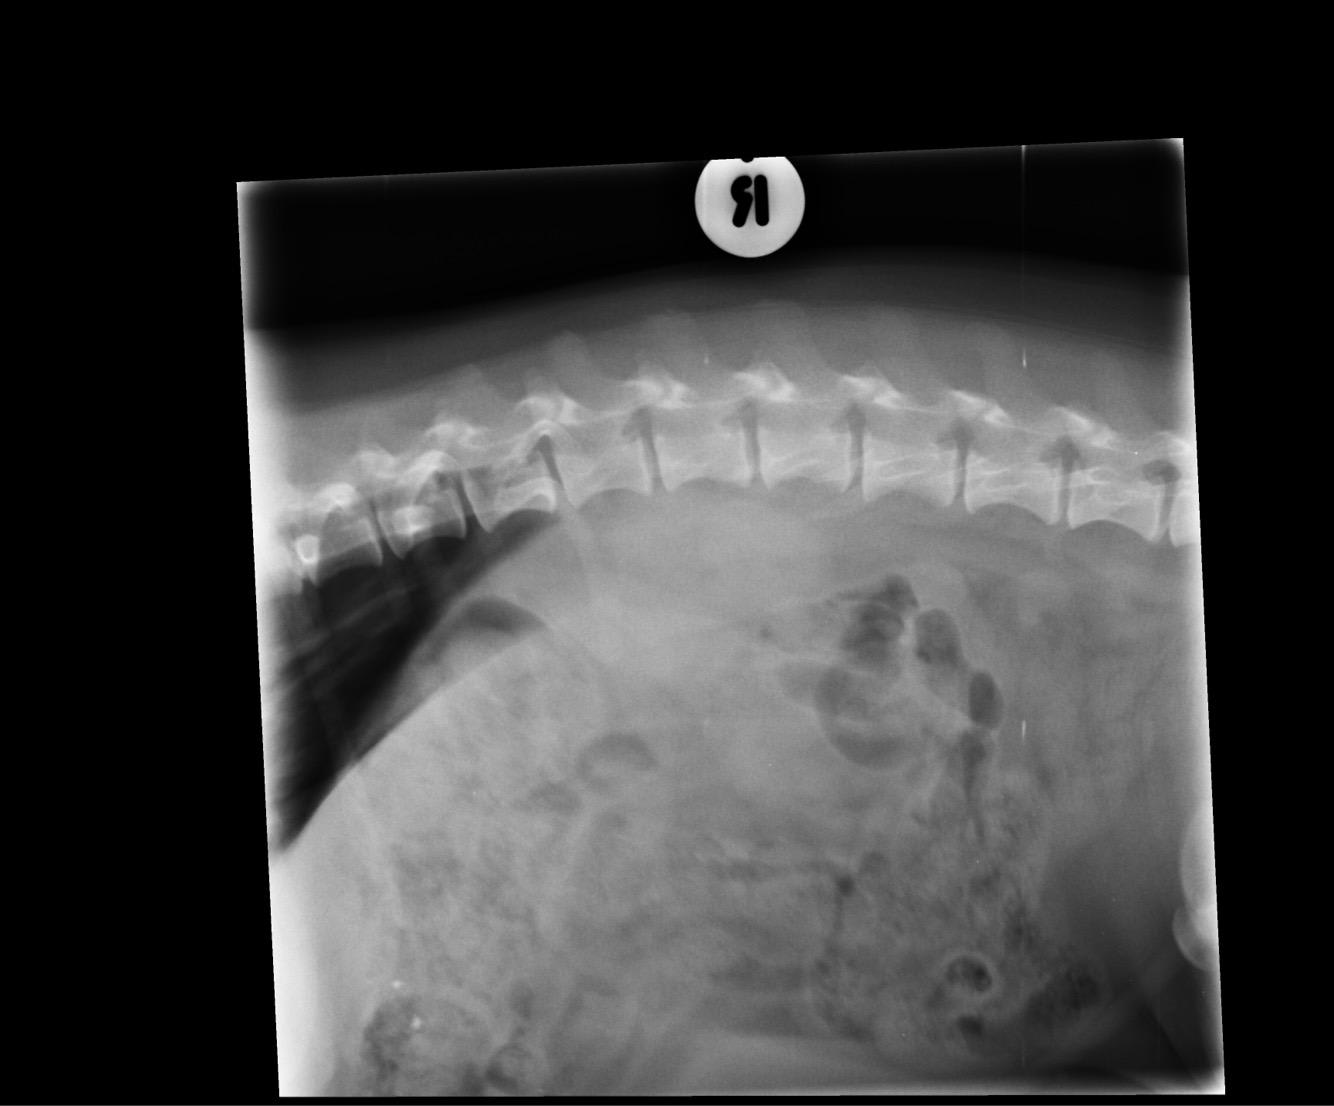

Pet's info: Dog | Dachshund | Male | neutered | 6 years and 6 months old | 20 lbs

Could you please tell me what you see in this X-ray and what we should do next? Thank you

It is not recommended to interpret x-rays without information about that is going on with the patient. If you would like to post more information about what is going on with Rolo, one of us will be happy to try to help you.